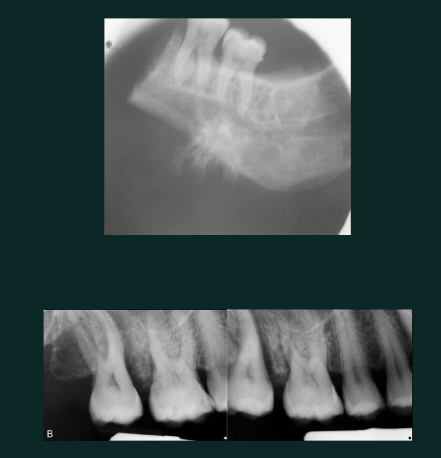

Simple bone cyst (traumatic bone cyst)

Developmental/odontogenic RL lesions

scallops between roots

vital teeth

uniocular RL

rarely any resorption or displacement of adjacent teeth

unlike OKC, SBC is NOT corticated or expansile